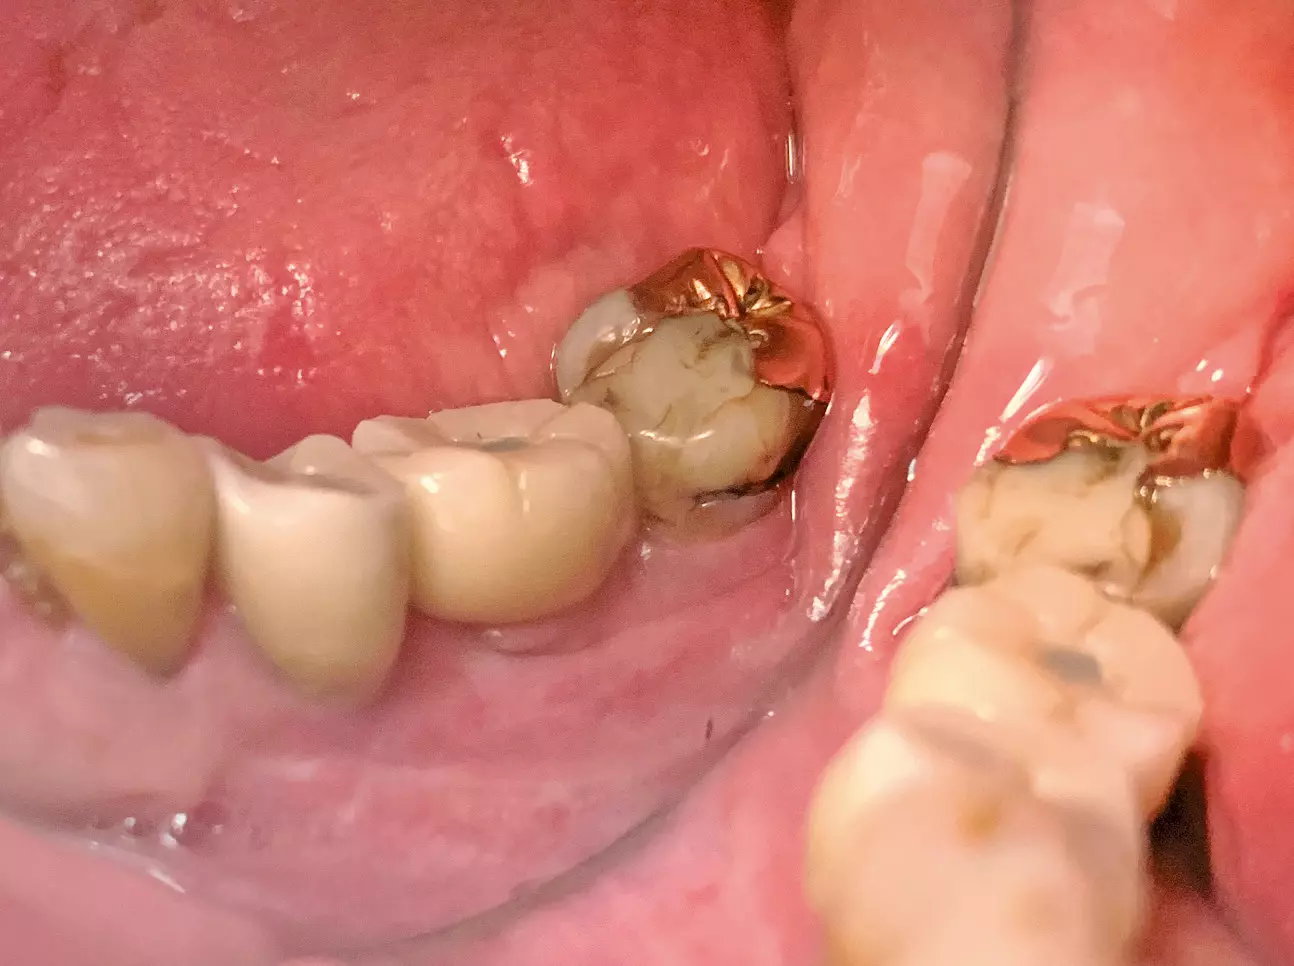

Zu allen Standardabutments (0°. 7,5°, 15°, 22,5°) existieren beim Myplant two-System passgenaue Kappen aus Gold, die als Friktionselemente (4° Konus) zur Retention der prothetischen Restauration geeignet sind (Abb. 6).

Diese Variante ist als besonders interessant einzustufen, da sie mit den vorhandenen Standardabutments durchgeführt werden kann, die auch die provisorische Restauration zur Sofortversorgung oder zum Knochentraining getragen haben („One Abutment One Time“-Konzept). Die Parallelisierung der frei einstellbaren, da nicht mit Index versehenen Abutments geschieht dabei direkt im Mund über optische Parallelisierungshilfen, die Abformung über präzise Transferkappen. Alternativ kann die Auswahl und parallele Positionierung der Standardabutments natürlich auch nach Übertragung der Implantatposition über einen Scan- oder konventionellen Abdruck durch das zahntechnische Labor vorgenommen werden, wobei die Rückübertragung der exakten Position über einen individuellen externen Index sicherstellt wird (Abb. 7).